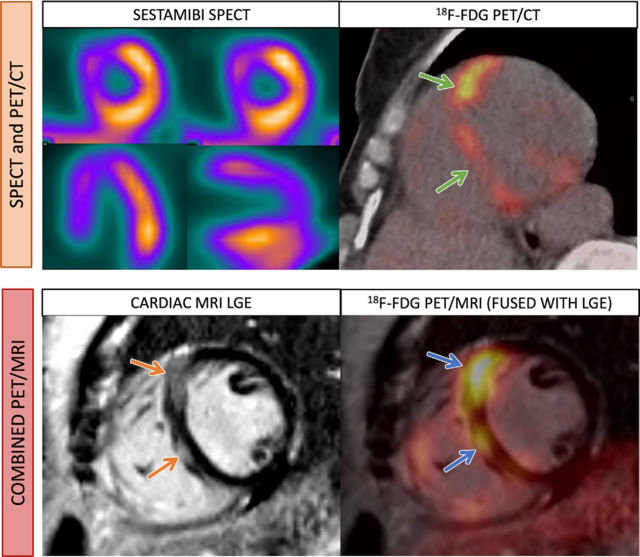

Enhance your business with our stunning commercial Cardiac Pet/ct collection of numerous professional images. optimized for commercial use with truck, vehicle, and automobile. ideal for corporate communications and branding. Discover high-resolution Cardiac Pet/ct images optimized for various applications. Suitable for various applications including web design, social media, personal projects, and digital content creation All Cardiac Pet/ct images are available in high resolution with professional-grade quality, optimized for both digital and print applications, and include comprehensive metadata for easy organization and usage. Discover the perfect Cardiac Pet/ct images to enhance your visual communication needs. Our Cardiac Pet/ct database continuously expands with fresh, relevant content from skilled photographers. Reliable customer support ensures smooth experience throughout the Cardiac Pet/ct selection process. Professional licensing options accommodate both commercial and educational usage requirements. Multiple resolution options ensure optimal performance across different platforms and applications. Regular updates keep the Cardiac Pet/ct collection current with contemporary trends and styles. Each image in our Cardiac Pet/ct gallery undergoes rigorous quality assessment before inclusion. Time-saving browsing features help users locate ideal Cardiac Pet/ct images quickly. The Cardiac Pet/ct archive serves professionals, educators, and creatives across diverse industries. Comprehensive tagging systems facilitate quick discovery of relevant Cardiac Pet/ct content.